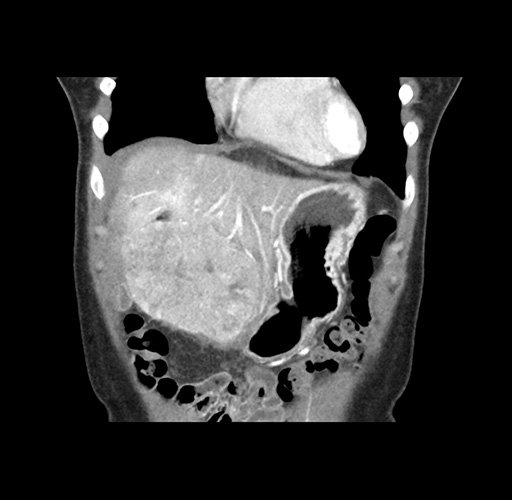

Imaging Analysis

Look through the patient's CT scan to identify any areas of concern for the necessary procedure.

Based on your CT findings, which issue(s) would give reason for "planned slowing down moment(s)" in this case?

Considering a standard left lateral sectionectomy procedure, what step(s) of the operation would you do differently in this case ?